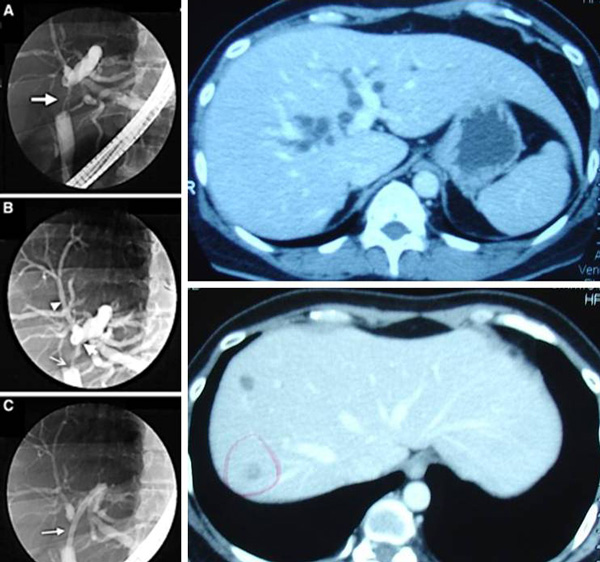

Hasil CT scan pada 28 Januari 2010 menunjukkan ada batu sebesar 6 mm di kantong empedu. Ditemukan juga adanya lesi hypodense sebesar 1 cm di segmen 8 pada organ hati nya. Ini kemungkinan bisa saja kista. Kondisi Saluran empedu secara umum melebar. Diameter maksimumnya adalah 16 mm. Ditemukan adanya massa 18 mm pada saluran distal.

Dari hasil pemeriksaan CT scan pada tanggal 9 Juni 2010 menunjukkan adanya lesi di segmen 7 dari bagian hatinya sebesar 15 x 10 mm. Kemudian keberadaan dari Kista yang sebesar 10 mm pada segmen 8 dari bagian hatinya masih tetap sama.

Selain itu terdapat beberapa kelenjar getah bening paraaorta yng membengkak dan terlihat dari daerah celiac yang turun menuju ke daerah hati dan hilus ginjal. Kelenjar yang terbesar berukuran sebesar 20,0 mm – yang lainnya berukuran lebih kecil dari 1 cm.